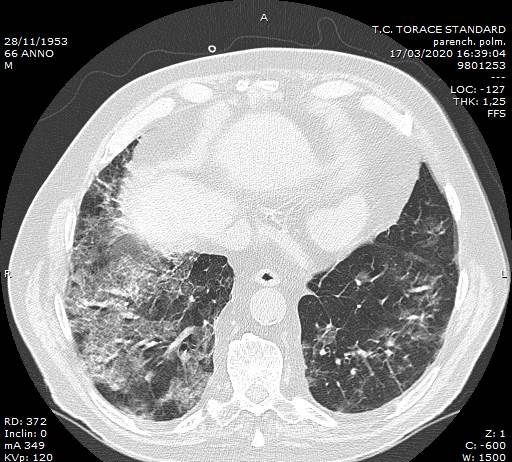

Maschio, 66 anni. In anamnesi: diabete mellito; ipertensione arteriosa;...